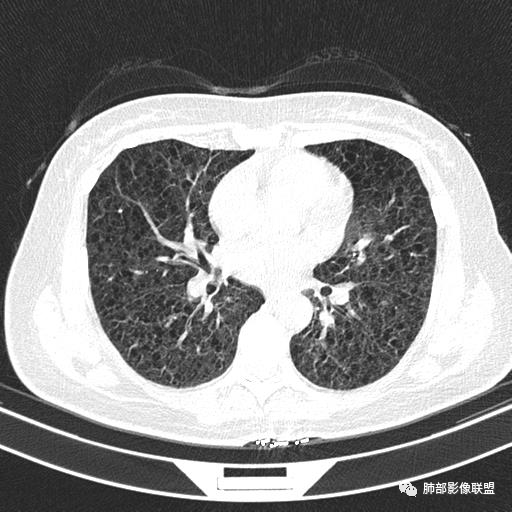

双肺弥漫囊腔,累及肋膈角,囊腔形态相对规则单一。

CT平扫示双肺弥漫分布大小不等囊状薄壁透光区,无内、中、外带分布差异,间质稍示增厚。拟LAM

女,46,活动性气喘1年。苯吸入史半年。胸部CT:两肺弥漫囊腔,上至肺尖,下至肋膈角,形态类似小囊腔。考虑:LAM,鉴别LIP,BHD,PLCH等。

双肺弥漫大小不一薄壁含气囊腔,囊间肺组织正常,正常肺背景,肺尖肺底受累;青年女性,气喘,支持LAM

CT表现:双肺弥漫大小不等的薄壁囊腔,囊壁<2mm,外形规则,血管影多位于囊腔周围,囊腔之间肺组织正常,随着疾病进展到晚期,囊腔变大、增多,不可胜数,囊腔可融合成较大的囊,与肺气肿相似,形成间质性肺纤维化。部分病例可出现结节影。